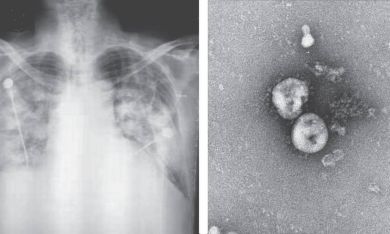

Casos suspeitos de coronavírus na região são descartados em exame

Os dois casos suspeitos de coronavírus em Santa Catarina divulgados pelo Ministério da Saúde nesta quarta-feira (29), foram descartados em exame laboratorial, informou a Dive/SC (Diretoria de Vigilância Epidemiológica). Trata-se de um casal que mora em São José, diagnostigado com gripe (Influenza B).

Um plano de contingência para síndrome respiratória aguda grave para atender e identificar casos suspeitos, foi ativado pela Dive/SC na terça-feira (28). O órgão ainda recomendou que a população evite viajar para a China, local de maior concentração da doença e onde o vírus se originou. Isso porque não existe, até o momento, vacina para prevenir a infecção.